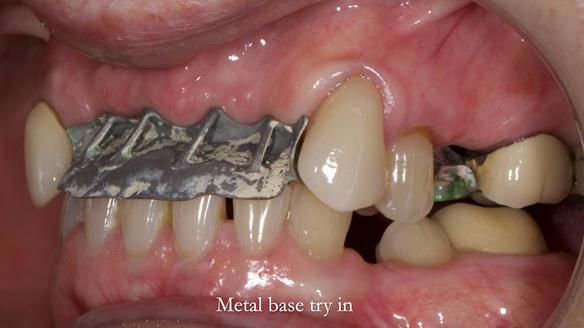

This is one of those cases that reminds me why I love removable prosthodontics. Pam was an absolute joy to treat — we were on the same page throughout. Her old upper flexible denture was loose, uncomfortable, and unaesthetic. We replaced it with a carefully designed metal-based upper partial denture/splint and new porcelain-bonded-to-zirconia (PBZ) crowns for the canines. The result is stable, comfortable, and natural-looking.

- Diagnosis and plan – Flexible upper denture ill-fitting with poor stability, retention, and appearance. Plan: metal-based upper partial denture/splint with lighter porcelain-bonded-to-zirconia crowns on UR3 and UL3.

- Metalwork framework try-in – to verify fit, path of insertion, and support.